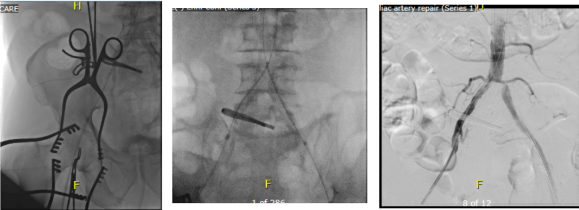

The hardest case that I have taken care of ever was at the Clinic a couple of years ago. The patient was a middle aged man who had ruptured an aortic aneurysm in another state some months prior and had undergone a repair complicated by a pancreatic injury along with some enterotomies resulting in a graft infection along with high output pancreatic and enteric fistulae from an open abdomen. He arrived cachectic, in septic shock and had a pseudoaneurysm from the distal anastomosis of a short tube graft. I immediately took him to the OR to place a stent graft across the pseudoaneurysm neck to prevent rupture and placed him on TPN to correct his cachexia. The abscesses and hematomata were drained percutaneously, and an effort was made to control the fistula with a heroic effort on the part of the ostomy team. He turned around and was able go to an LTAC on TPN and antibiotics. There he gained twenty pounds and returned flush and active. Stage two was three months later and done to replace the still infected grafts with cryopreserved homograft. I did this via a right retroperitoneal approach as the left side and abdomen were a mess from the inflammation. After I removed the grafts and sewed in the homograft, general surgery reorganized his bowel and discovered that he only had about 30cm of useable small bowel and would be on TPN for life. But he was alive and learning to walk again, and eventually came back 6 months later for follow-up and gave me a hug.